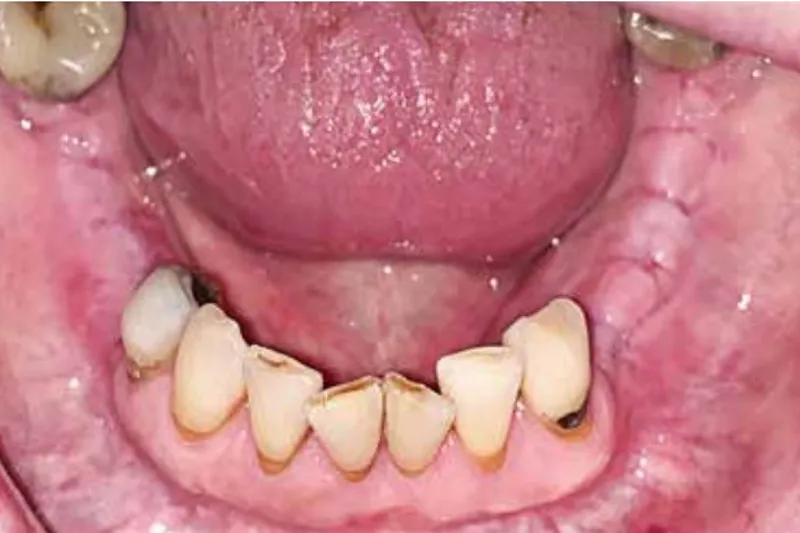

RESULTATER – Samlet indgår 356 patienter med MRONJ i studiepopulationen, 327 i HDAR og 29 i ADAR. Patienterne er overvejende i AR i relation til myelomatose, bryst- eller prostatakræft. Kvinder udgør 62 % fordelt på 60 % i HDAR og 86 % i ADAR. Gennemsnitsalderen ved indledende besøg er 68,7 år for patienter i HDAR og 71,0 for patienter i ADAR. I henholdsvis 58 % (HDAR) og 62 % (ADAR) af tilfældene er osteonekrosen lokaliseret i mandiblen. Blokresektion og sekvestrektomi er de hyppigst anvendte metoder i behandlingen. Den gennemsnitlige levetid efter indledende besøg i afdelingen er 15,7 måneder længere for kirurgisk behandlede patienter sammenlignet med konservativt behandlede.

Osteonekrose i kæberne er en alvorlig bivirkning til antiresorptiv behandling, og kendskab til patientgruppen med henblik på tidlig opsporing og behandling er afgørende. I takt med at behandlingsmulighederne forbedres, udvikler stadig flere patienter MRONJ. Behandling med kemoterapi, steroider og methotrexat samt nyere medikamenter som monoclonale antibodies og proteinkinasehæmmere ser alle ud til at kunne påvirke udviklingen af MRONJ. Når den medicinske patient møder i klinikken, er det derfor særlig vigtigt at have opmærksomhed på områder med spontant opstået blottet knogle, uforklarlige smerter, sensibilitetspåvirkning og løsning af tænder. Ligeledes er det vigtigt at behandle infektionstilstande og henvise for fjernelse af ikkebevaringsværdige tænder.Medication-related osteonecrosis due to adjuvant or high dose antiresorptive treatment